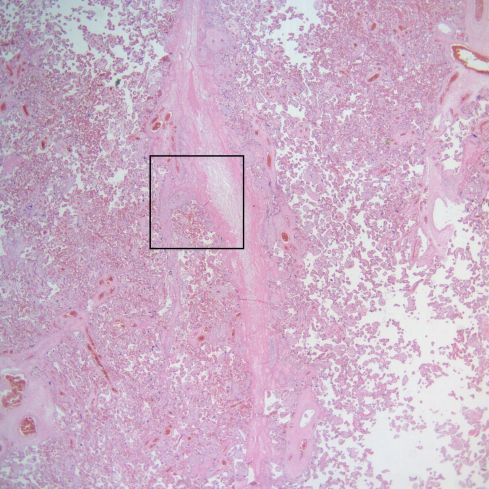

The name simply implies inflammation that occurs in the placental villi. This broad concept is subcategorized into pathologic entities. These subcategories for villitis were first established by Altshuler and Russell 1. Their category of diffuse villitis, which was described primarily as villous edema and immaturity, and is not usually considered villitis today. Their category of acute villitis is also not usually considered villitis as much as a rare component of ascending infection and will be considered in that chapter, but the appearance at low magnification can mimic chronic villitis

Fig 1) At low magnification, there appears to be a nest of typical chronic villitis. (H&E, 10x)

Fig 2) At high magnification, the villitis demonstrates a high percentage of neutophils consistent with acute villitis. (H&E 40x)

(Fig 1-3). Villous edema and acute inflammation may be a minor component of other categories of chronic villitis.